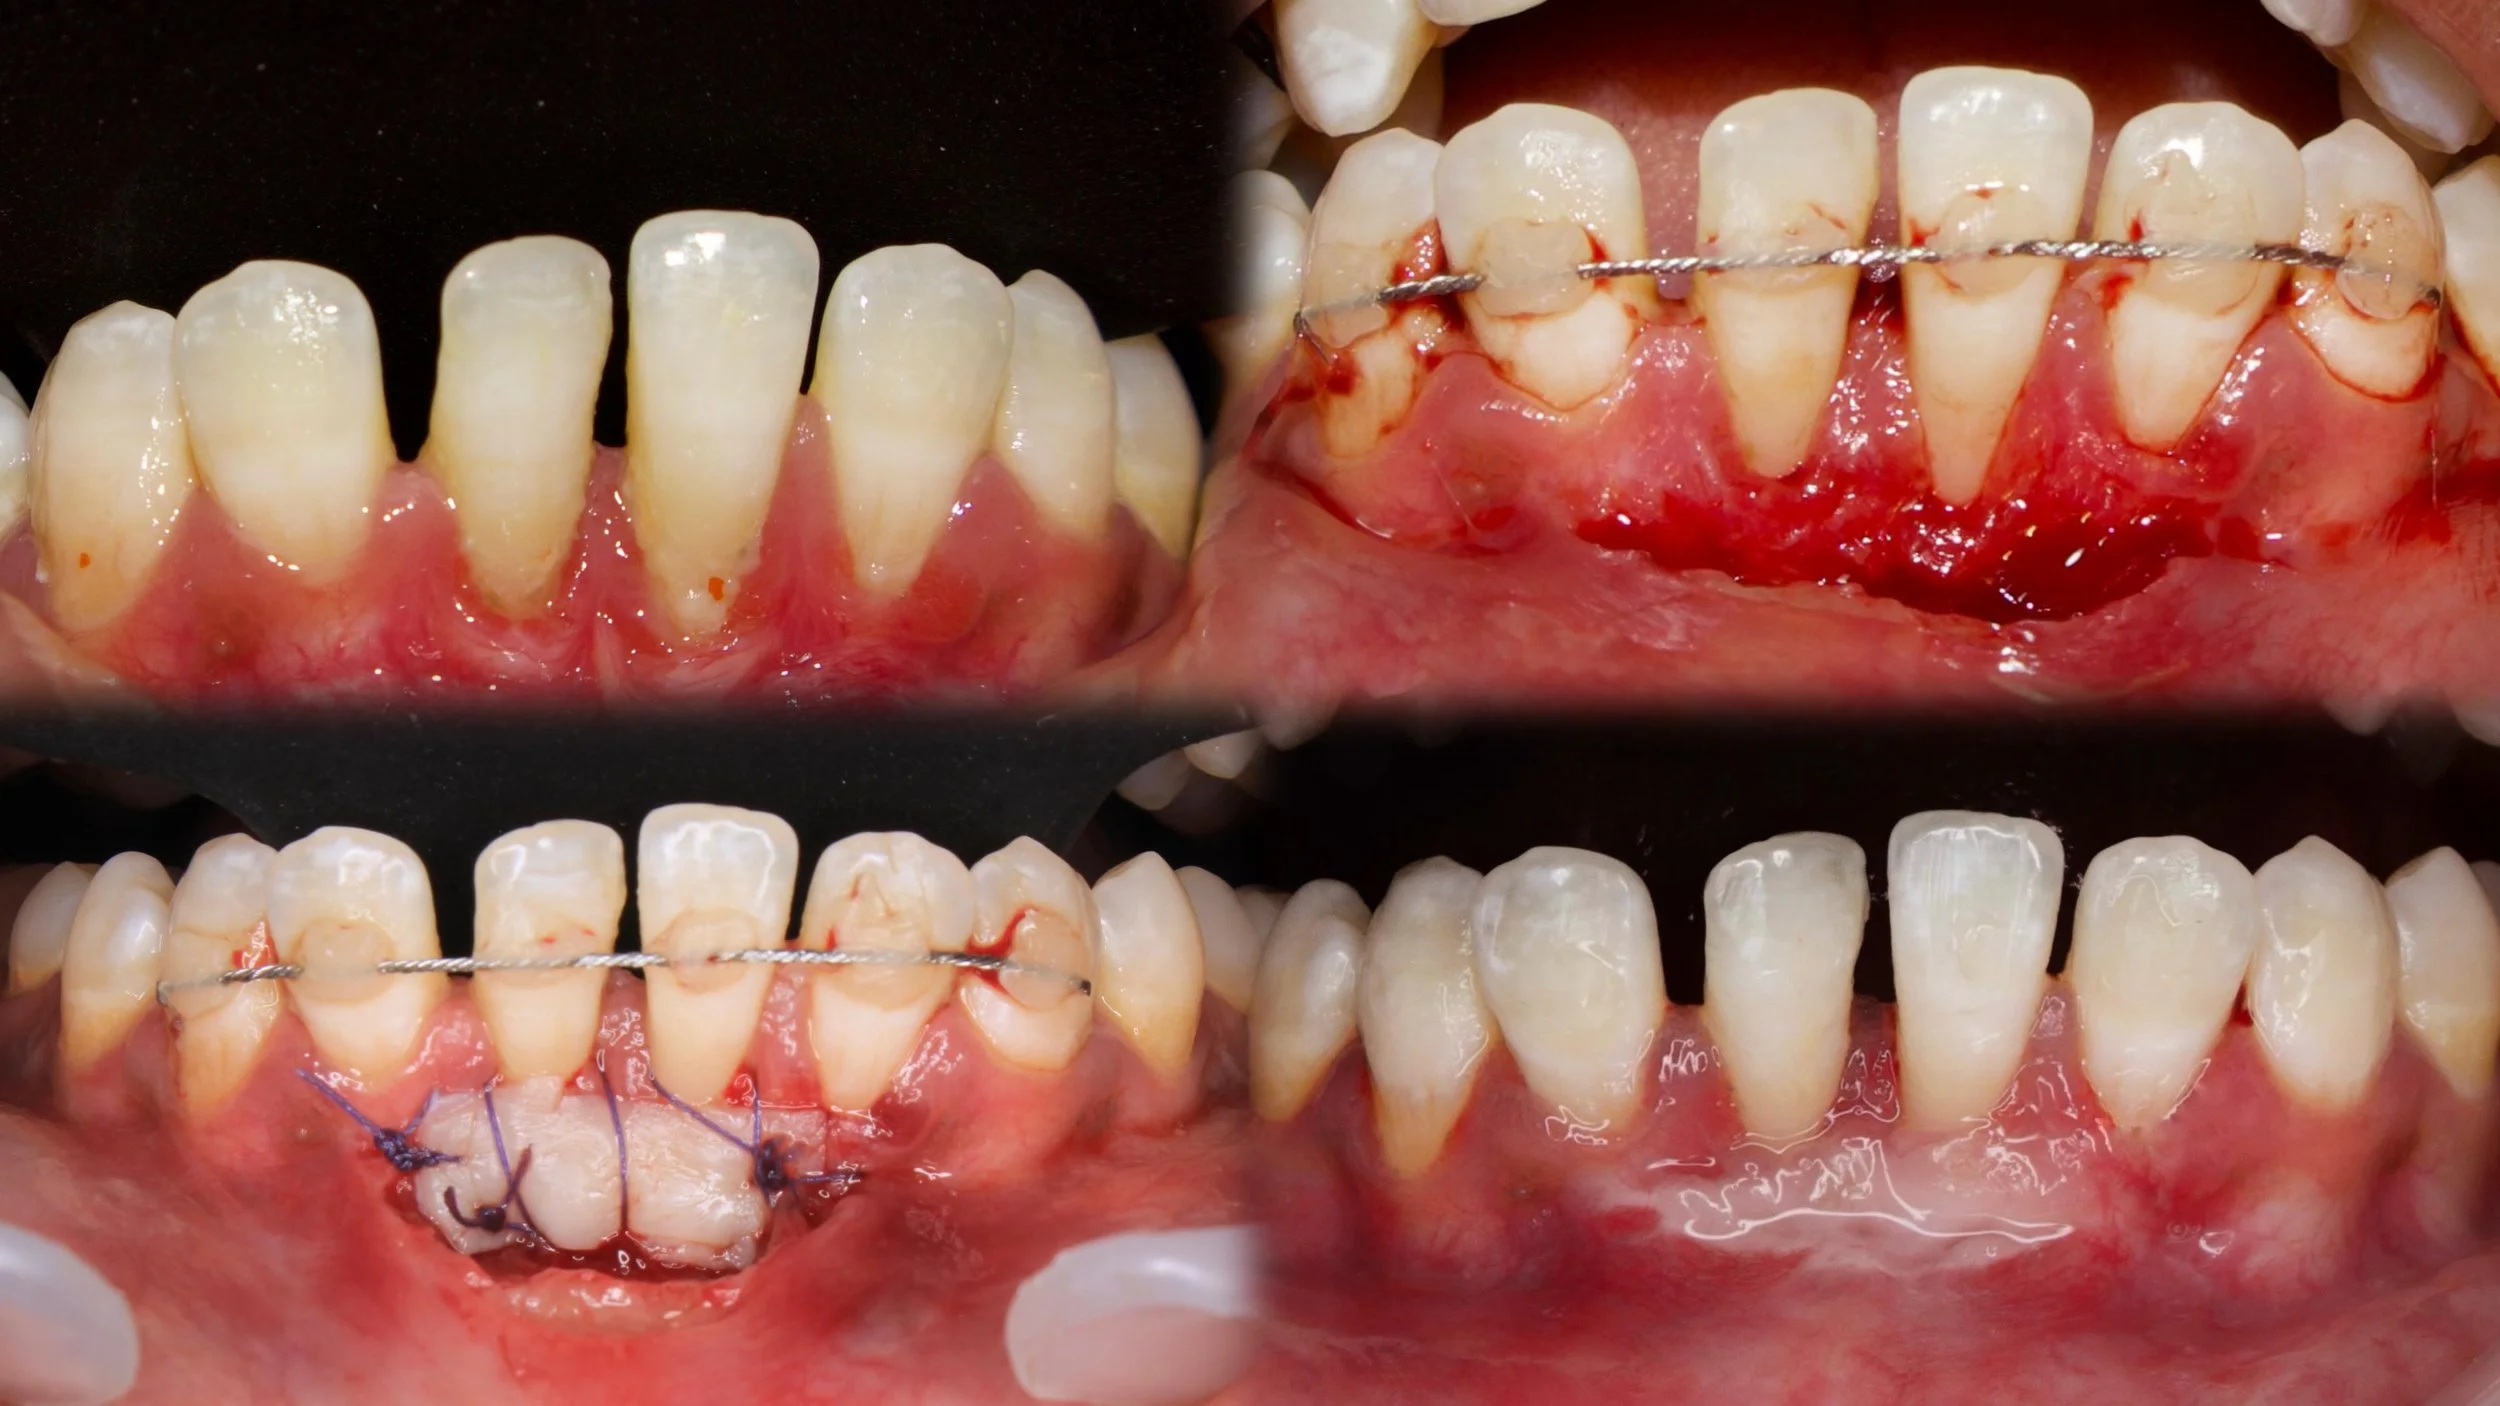

Free gingival graft done to augment the zone of attached gingivaβ€”ensuring long-term periodontal stability.✨

Case done y Dr Nainpreet

Periodontics SaveethaJune 30, 2025